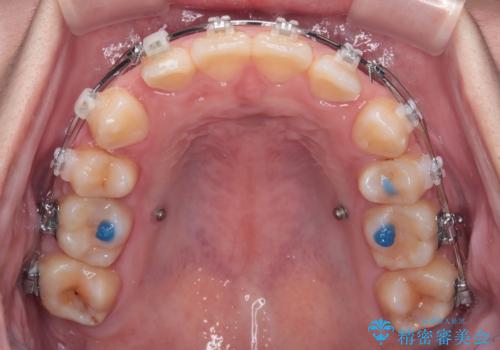

- 矯正装置

- クリアブラケット

- 治療計画

- 転勤により東京へ移られることになり転院先を探されていた患者様です。ワイヤー矯正の途中での急な転勤なうえ、今後2~3年以内に再度転勤になる可能性もあるというご事情でした。

そのため、限られた期間内に効率よく治療を完了するために、「抜歯スペースの確実な閉鎖」「深い噛み合わせ(過蓋咬合)の改善」の2点を主軸とした治療計画を立てました。